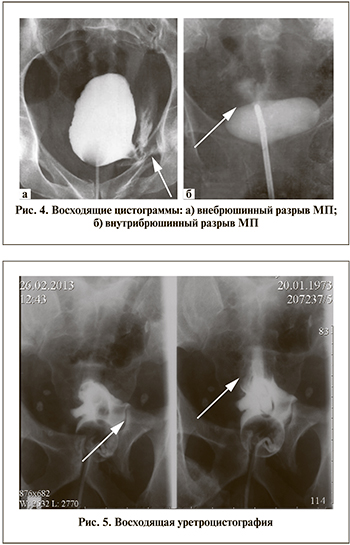

Основные травмирующие факторы мочевого пузыря (МП) при ДТП – ремень безопасности, в особенности при переполнении МП, а также кости таза. Внутрибрюшинные разрывы МП диагностируются у 36% пострадавших, внебрюшинные и сочетанные у 57 и 6% соответственно [11, 12].

Рентгенологические признаки (цистограмма) видов повреждения МП представлены на рис. 4.

Основные клинические признаки травмы МП – макрогематурия. При их наличии в сочетании с переломами костей таза мы всегда выполняем КТ-цистографию, а по показаниям и другие инструментальные методы диагностики (внутривенная урография, УЗИ, ангиография, МРТ) [13]. Объем лечения пострадавших с повреждением МП определяется в зависимости от периода ТБ и вида повреждения МП. Приоритетны мероприятия по стабилизации состояния пострадавшего и компенсации жизненно важных функций, угрожающих жизни. При внебрюшинном разрыве мы устанавливаем уретральный катетер.

Пострадавший К. 1969 г.р. поступил после ДТП в травматологическое отделение госпиталя с переломами бедра и лонных костей. Наблюдалась макрогематурия. Была выполнена восходящая уретроцистография (рис. 5), при которой диагностирован разрыв стенки МП, установлен мочевой катетер.